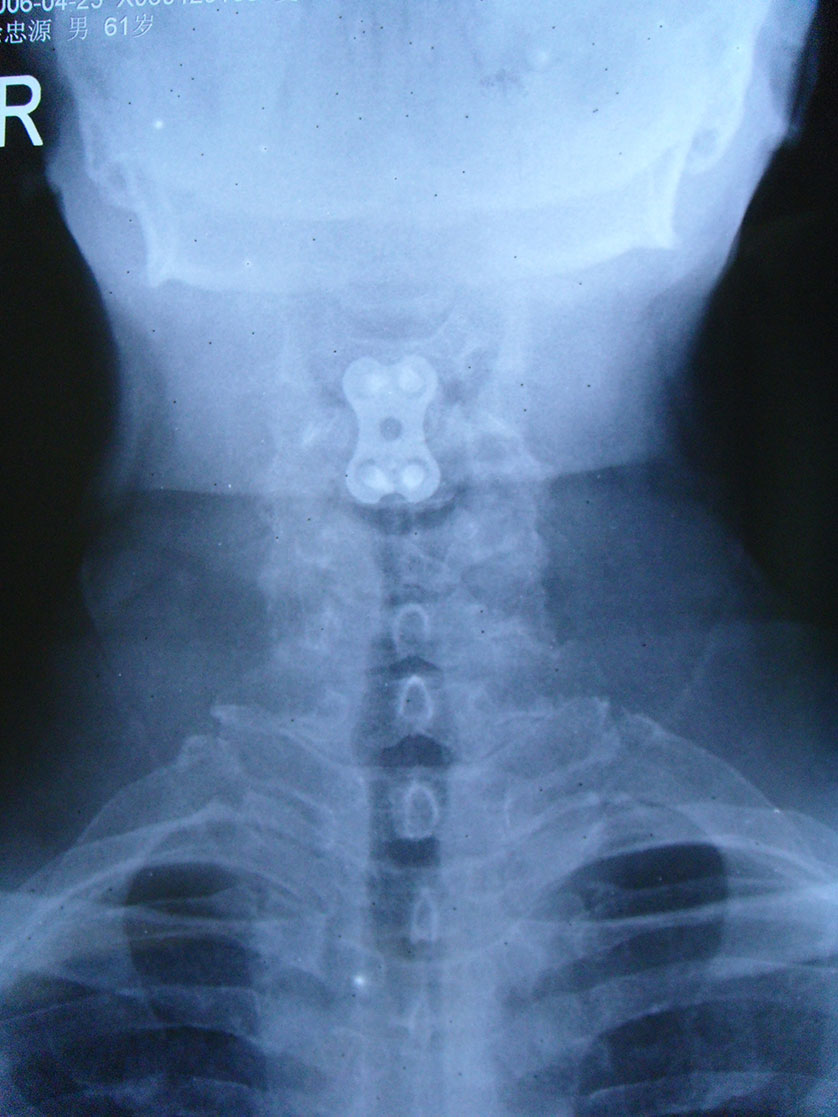

徐**,男性,于2006年2月24日因第3/4颈椎椎间盘突出症,颈椎前路椎间盘切除,同种异体骨椎体间植骨融合内固定手术,术后2个月,11个月及4年半随访植骨块愈合良好